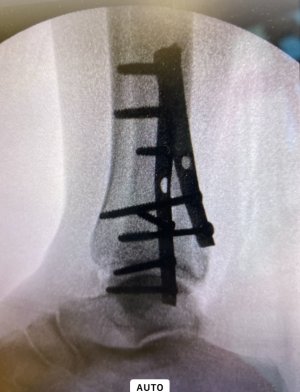

Couple of days later, get on flight, home. Injury not doing so well but get checked into NHS system, CT scan, admitted to hospital immediately with a worrying Pilon fracture. Operation at the weekend and at long last home just yesterday.

Anyway, finally moving forwards now but that’s one not to forget in a hurry. As for holiday snaps, this is a beauty for the album: